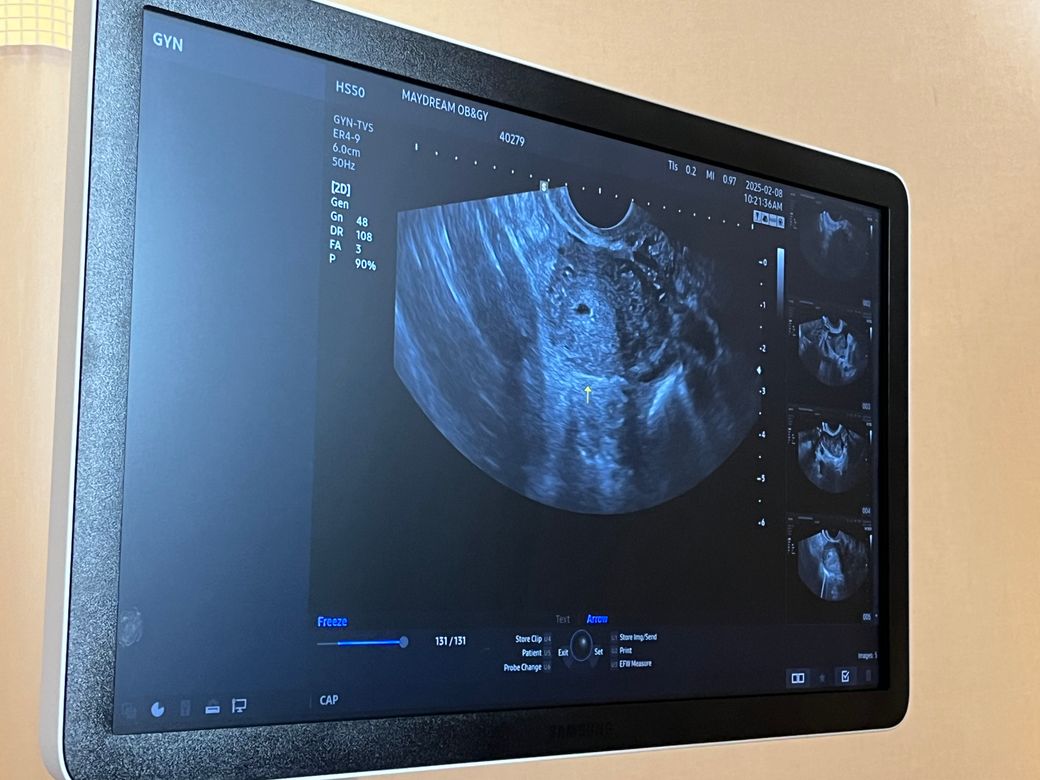

초음파 아기집 크기작은데 괜찮은가요?

주수로는 5주차인데 의사가 아기크기가 3주차크기로

작다고 했어요 0.97이라는데 괜찮게 잘크고 있는걸까요??

자궁외임신 유산 가능성은 없는거겠죠? 출혈은 아직까지

한번도 없었습니다.

• 2번 째 사진

아기집이 정상적으로 자궁내 확인되었다면 자궁외임신 가능성은 배제 할 수 있겠으나 지속적인 초음파 검사를 통해 정상적으로 아기집이 커지는지 확인이 필요하겠습니다.